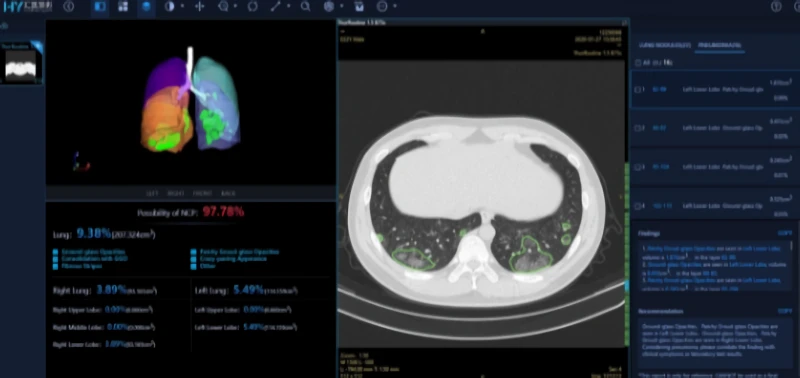

Here's an example from the paper Deep Learning System to Screen Coronavirus Disease 2019 Pneumonia, which works on 2-D slices of the CT scan.

The paper first segments the lung using image preprocessing methods. Then regions of interest are extracted using the VNET20-based segmentation model VNET-IR-RPN17. The model itself was trained for extracting ROIs from pulmonary tuberculosis, but it was found that it worked well enough for the COVID-19 use case as well.

Then each RoI is run through a classification model, where we get the class probabilities. There can be one or more RoIs, giving us multiple probabilities. These probabilities are then combined using something called a Noisy-or-Bayesian function. More details about this can be found in the paper linked above.

The paper also leverages the fact that for coronavirus, often the opacities are found around the edges of the lungs, which is used as an input to the network at a later phase. The details on how exactly this distance is calculated can be found in the paper.

The network architecture is inspired by ResNet, with local-attention on the final classification layer.